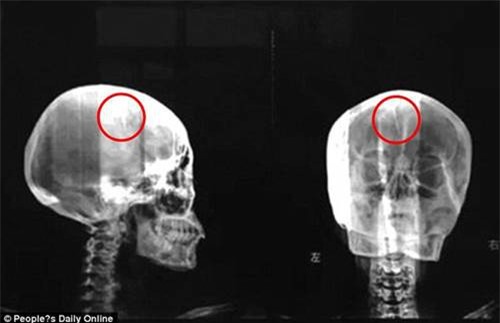

(DNVN) - Bị chứng đau đầu kinh niên suốt 40 năm, người phụ nữ quyết định đi khám thì bàng hoàng khi nghe các bác sĩ kết luận trong não của mình có một chiếc kim dài 4,5 cm.